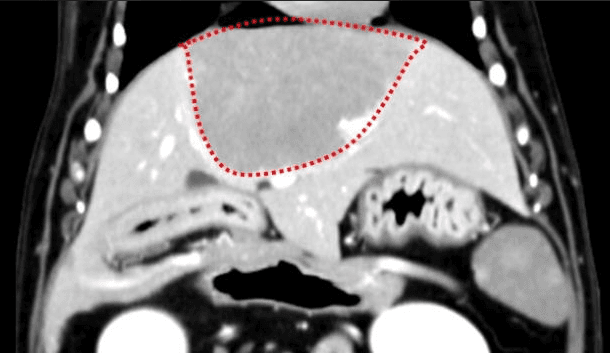

간, 담도 수술은 수술뿐만 아니라, 수술 후 중환자 관리도 중요하기 때문에 외과와 내과의 협진이 매우 중요합니다. 동탄시티동물의료센터에서는 최신 수술 장비의 도입으로 간담도 수술에서 출혈 및 부작용을 최소화 하였으며, 수술 후 협진 시스템을 통해 수술 후 관리에도 최선을 다하고 있습니다.

간종양

최고 사양 영상 장비를 활용한 정밀한 전이 평가

외과 협진 시스템을 통한 신속한 종양 수술

동탄 1 신도시 최초 Aquilion CX/128 slice CT를 동물병원에 도입하였습니다. 최고 사양 CT 모델 Aquilion CX/128 slice를 활용하여 0.5 mm의 얇은 128개의 단면 영상을 신속히 획득 할 수 있어 마취 시간을 단축시킬 수 있습니다. 또한, 128 슬라이스의 고화질의 CT 영상을 통해 영상 왜곡을 최소화하고 X-ray에서는 확인하기 힘든 5 mm 이하의 미세 병변도 확인이 가능하여 정확한 진단을 할 수 있습니다. 심화 진단이 필요한 경우, 조영제 인젝터를 통한 동맥기 촬영으로 종양 유래 확인, 간 질환 진단, 심혈관계 진단이 용이합니다. 저희 동탄시티동물의료센터에서는 본원 환자뿐 아니라 1차 동물 병원과의 CT 촬영 의뢰 시스템을 통해서 원활한 협진이 가능하도록 최선을 다하고 있습니다.

0164 채널 CT 촬영을 통해서 신속하게 고화질 영상을 얻어, 종양 유래 확인 및 전이 평가, 간문맥단락증(PSS), 선천적 뼈 기형과 같은 심화된 진단을 할 수 있습니다.